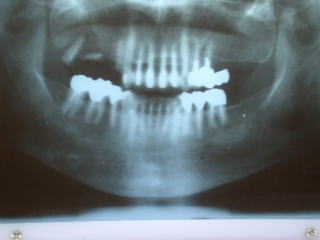

●インプラントのレントゲン写真例

上の前歯の例です。

左上の入歯が見た目、噛合せとも満足できず、左上前歯部にインプラントを植立。

入歯をブリッジにすることにより不満を解消できました。